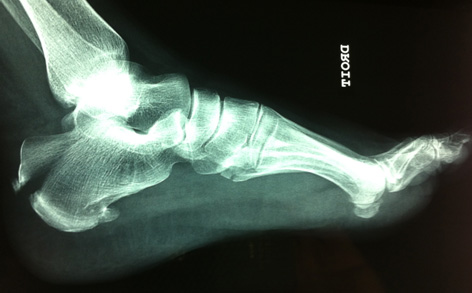

Mme I. âgée de 72 ans mesure 1,54 et pèse 108 kgs. Elle a fait une mauvaise chute de sa hauteur.  Elle ne se souvient plus du mécanisme exact mais elle n’est pas tombée sur ses talons.

Elle a ressenti une douleur du mollet puis du talon avec impotence fonctionnelle. On peut, a posteriori, imaginer une rétraction brutale du tendon achilléen.

Voici les radiographies effectuées :